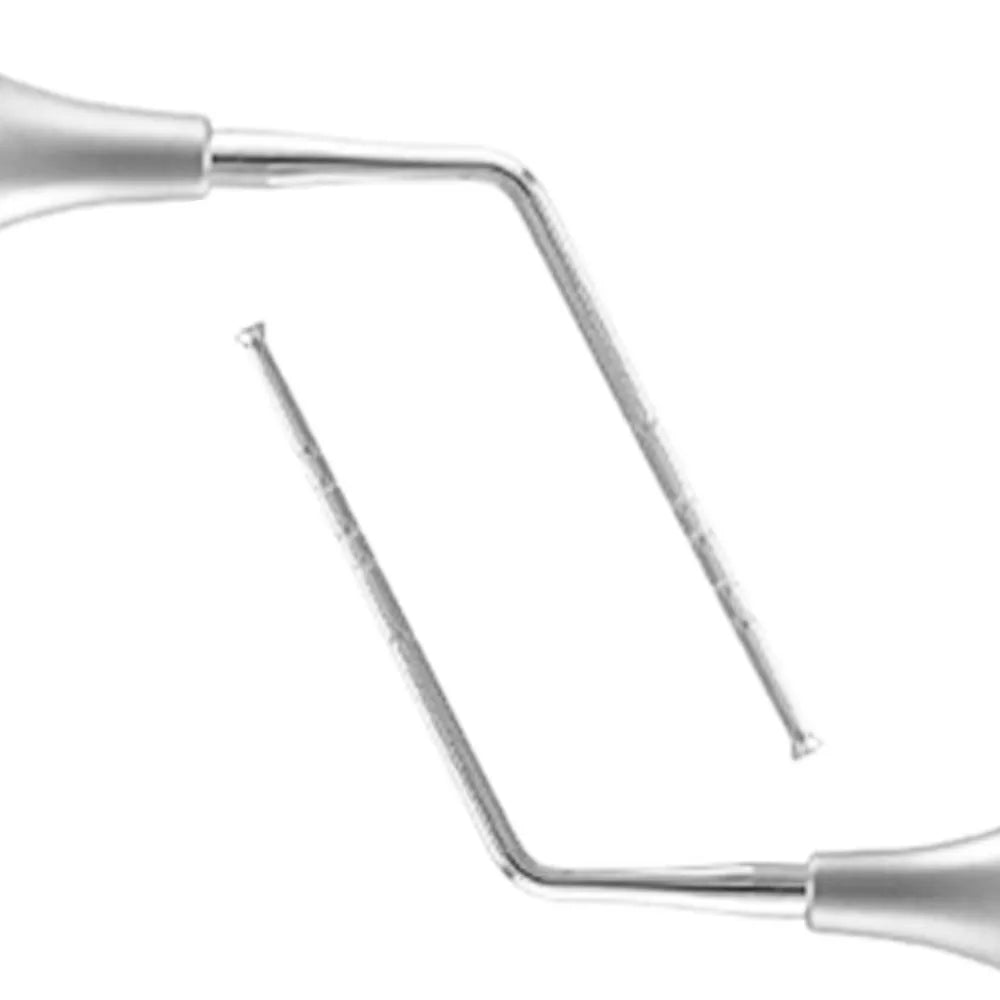

GDC Depth Measuring Gauge 1.2Mm PCP1301

GDC Depth Measuring Gauge 1.2Mm PCP1301

Depth Measuring Gauge 1.2mm GDC PCP1301

Used for general-purpose measurements, both in the clinic or for other purposes, to establish an accurate measurement, e.g., internal and external diameter, length, depth, or thickness. Instrument to measure the depth of the bony tunnel.They are manufactured from selective stainless steel by skilled workers with modern machines, keeping control of production and quality at every step to guarantee a supply of Instruments with utmost precision.

- Type: Depth Measuring Gauge

- Category: Implantology

- Material: Stainless Steel

- 1 x Depth Measuring Gauge 1.2Mm PCP1301